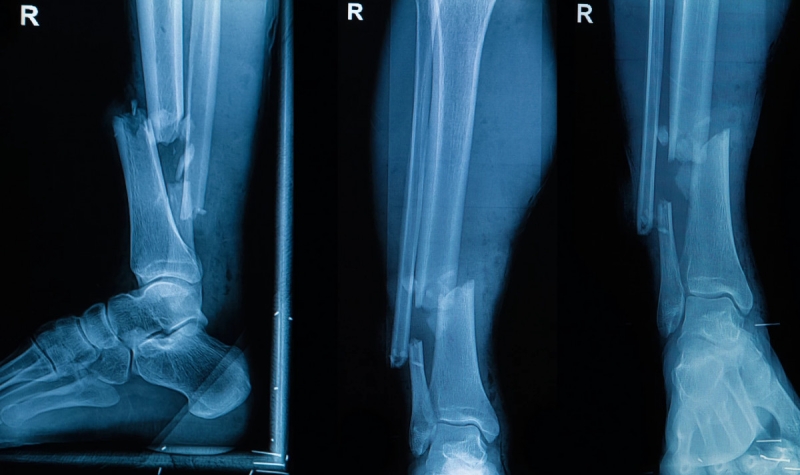

Группа ученых из США и Южной Кореи провела первые успешные испытания новой технологии по созданию костных имплантов непосредственно в месте повреждения костей. Они модернизировали клеевой пистолет, чтобы наносить специальный состав в нужную область в требуемых количествах. Он не заменяет собой кость, но позволяет устранить повреждения на время, пока костная ткань не разрастется и не заполнит этот участок.

Главное преимущество технологии в возможности отказаться от громоздких конструкций для фиксации обломков костей, а также сократить время лечения повреждений. Имплант формируется хирургом прямо во время операции, в организм не добавляется ничего лишнего, кроме небольшого объема вещества для замещения поврежденных частей костей. Процесс занимает считанные минуты, затем в течение 12 недель формируется новая структура, когда композит становится каркасом, на котором нарастает новая костная масса.